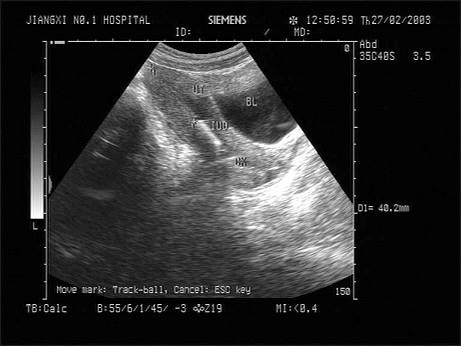

问题 女性,43岁,因月经时间长就诊。超声检查如图,最可能的诊断为?(?)

选项 A.节育环下移 B.子宫内膜癌 C.子宫肌瘤 D.宫腔残留 E.子宫内膜钙化

答案 A